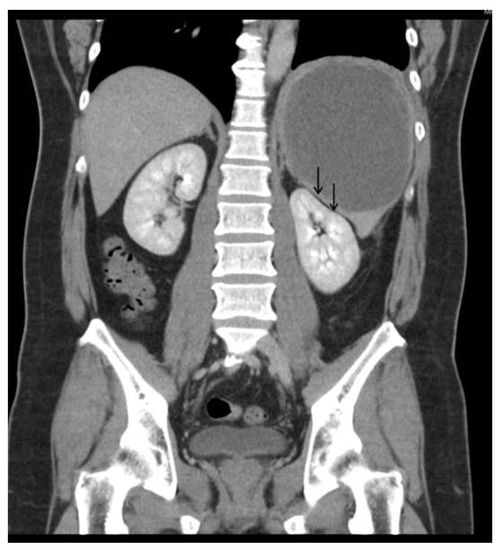

Figure 3.

Abdominal CT scan showed the mass was pushing the left kidney inward and down.